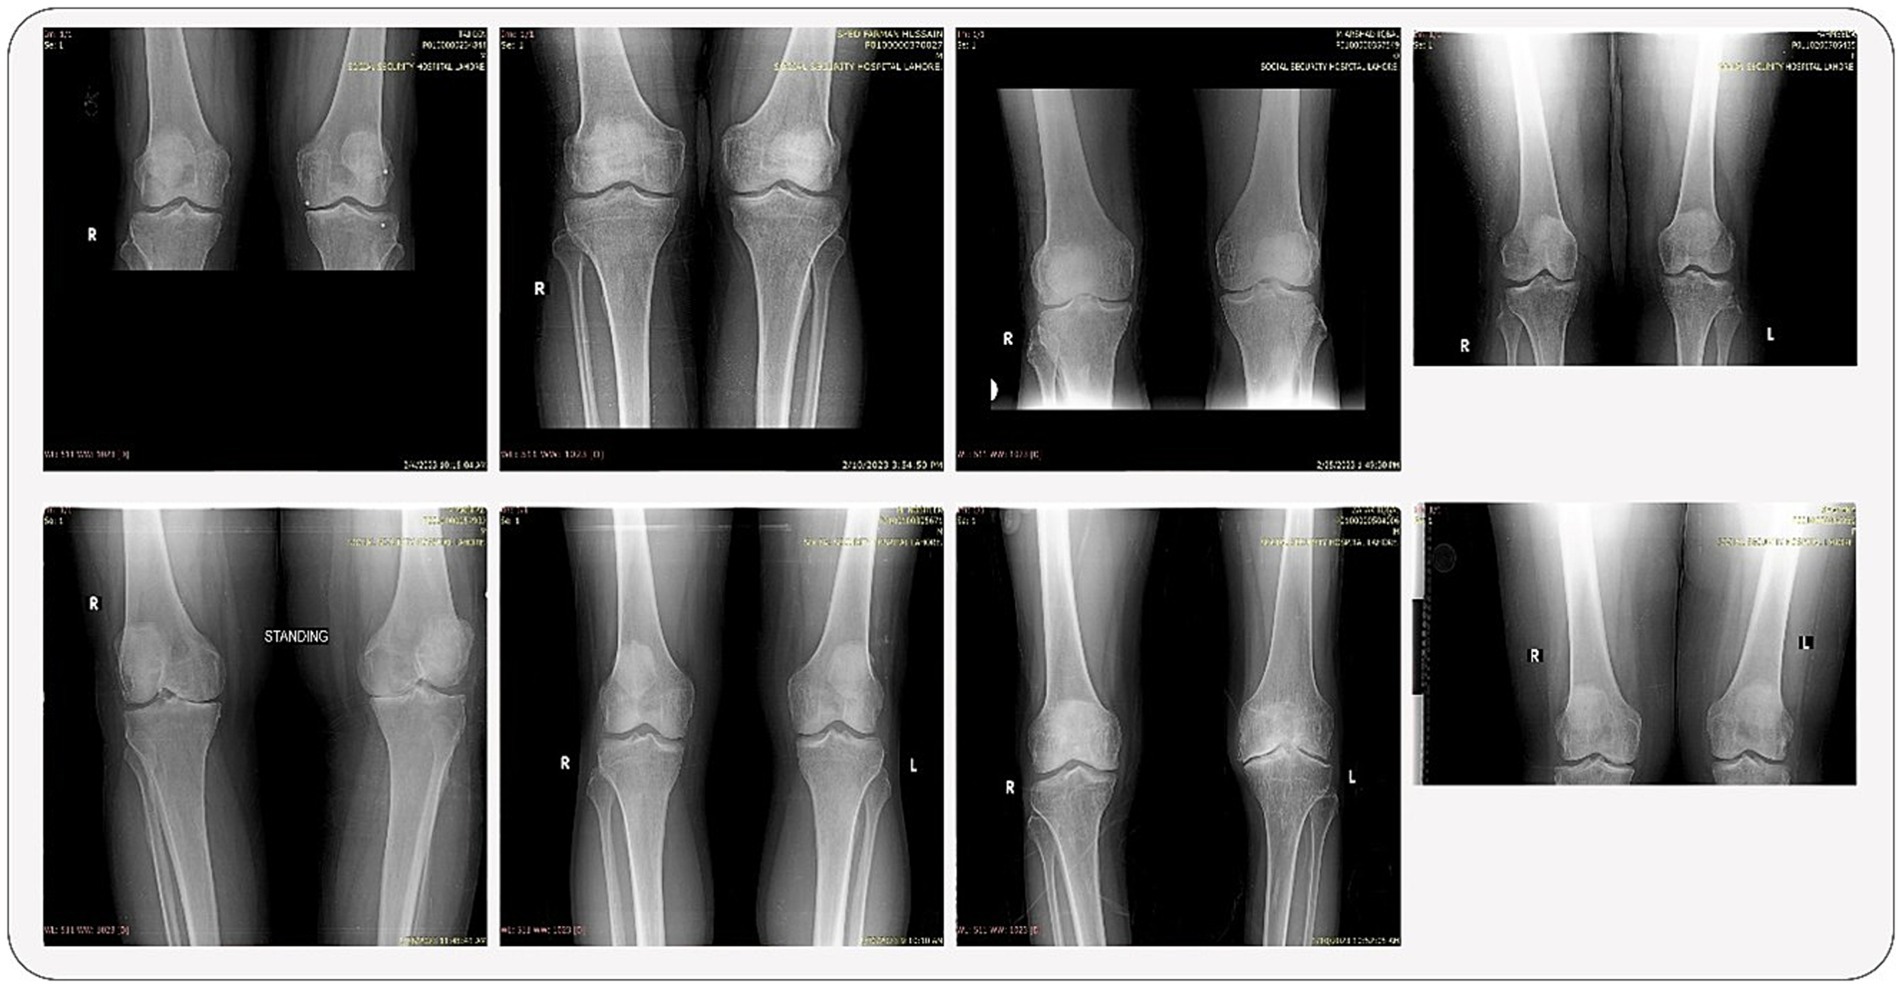

2.5 Data samples

This section provides a brief overview of the dataset’s composition and variety. Some samples from the dataset are displayed, offering a visual depiction of X-rays with varying grades. With images that show different levels of illness progression, these samples demonstrate the dataset’s heterogeneity. These samples give readers a first sense of the intricacy of the dataset, laying the groundwork for the subsequent approaches and conclusions described in the study. The samples are shown in Figure 2.

Figure 2

X-ray images of a person's knees in various positions. The images show anterior, lateral, and standing views of both knees, labeled with right (R) and left (L) indicators. The X-rays highlight the knee joints and surrounding bones.

Figure 2. Some random samples from the original dataset.